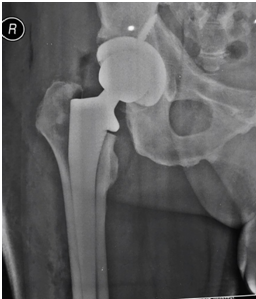

Metode Baru, Operasi Penggantian Pinggul dengan Minimal Invasif

Jakarta - Dr. Lee Woo Guan yang merupakan salah satu dokter ahli spesialis ortopedi terbaik di Malaysia terus berupaya memberikan pelayanan lebih maksimal. Salah satunya dengan memperkenalkan teknologi terkini yaitu 'Operasi Penggantian Pinggul' dengan metode Minimal Invasif (Minimal Invasive Hip Replacement).Semua pasien dapat mengalami nyeri pada pinggul dikarenakan banyak sekali…